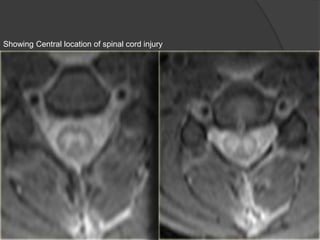

Showing Central location of spinal cord injury

Showing Central locationof spinal cord injury